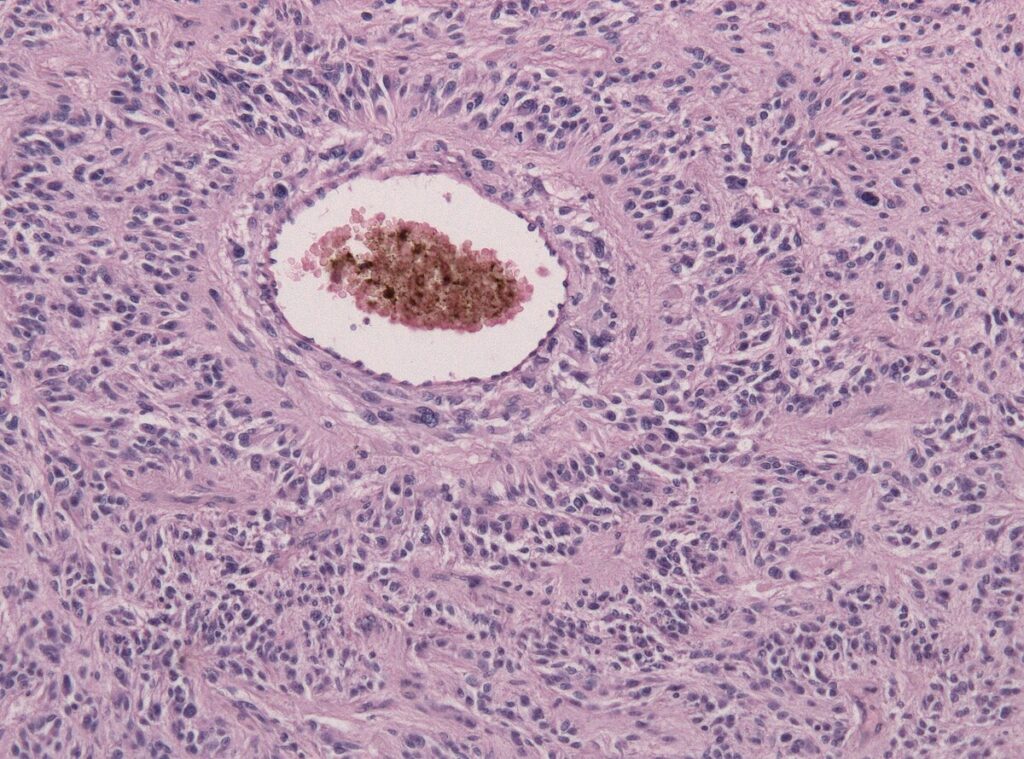

Lékařský tým z Mass General Brigham využil terapii CAR-T, personalizovanou léčbu, která využívá imunitní systém pacienta k boji proti rakovině. Tento proces zahrnuje extrakci T-buněk pacientů, jejich modifikaci a následné postupné reintrodukci do krevního oběhu. Tyto upravené buňky pak mohou identifikovat a napadat rakovinné buňky.

Tři pacienti, kteří byli součástí klinické studie známé jako INCIPIENT, byli léčeni buňkami CARv3-TEAM-E T. Tato varianta stávající terapie CAR-T zahrnuje navíc do každého pacienta infuzované další protilátky. Studie zaznamenala u pacientů dramatické snížení nádorů po jediné léčbě, přičemž u jednoho pacienta nádor téměř zcela zmizel.

Dr. Bryan Choi, neurochirurg z Mass General Brigham, prohlásil: „Platforma CAR-T revolučně změnila náš pohled na léčbu pacientů s rakovinou. Nicméně, pevné nádory jako glioblastom zůstaly obtížně léčitelné, protože ne všechny rakovinné buňky jsou přesně stejné a buňky uvnitř nádoru se liší. Náš přístup kombinuje dvě formy terapie, což nám umožňuje léčit glioblastom širším a potenciálně účinnějším způsobem.“